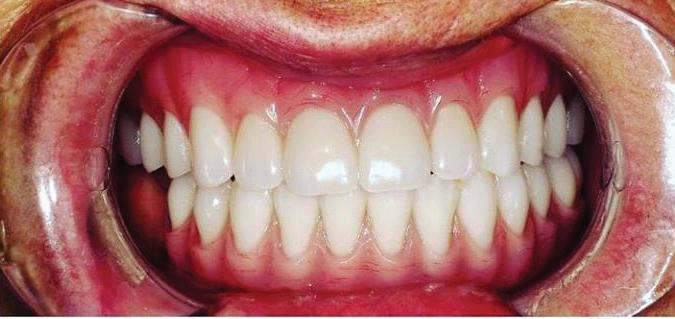

Can just four implants replace all of the teeth on the top or the bottom of your mouth? Thanks to advances in dental implant technology, that answer is a resounding yes.

Believe it or not, tooth loss is extremely common among adults, especially as we age. In fact, more than 35 million people in America are missing all of their upper and/or lower teeth. Rather than living with the discomfort and hassles of dentures, many people are opting for what is called “all-onfour” dental implant restoration.

All-On-Four: One Full Arch Of Teeth, Four Dental Implants

A Reason To Smile Again

able technique for replacing teeth, you should first understand what a dental implant is. An implant is a small titanium screw that fits inside your jawbone and replaces the root-part of a missing tooth. Minor surgery is required to insert the implants. Once the implant is in place, a crown is attached to give you a highly realistic-looking and functional prosthetic tooth.

Here’s where it gets really interesting: You do not need a dental implant for each and every one of your missing teeth. All you need is four precisely placed implants on the top of your mouth, and four on the bottom, to restore your full smile. That’s the beauty of the all-on-four. And because the implant is made of titanium, it has the unique ability to fuse to living bone and function as part of it. So eventually, the dental implant becomes part of the jawbone and serves as a strong, long-lasting foundation for your new teeth.

Besides ensuring that your implants are permanently fixed in place,

this bone fusion has another important benefit: it prevents future bone loss in the jaw. This helps to maintain a more youthful facial structure – and better oral health. But perhaps the biggest surprise about the all-on-four is how quickly it can transform your life.

All-On-4 Dental Implants: A Reason To Smile Again

To fully understand this remarkable technique for replacing teeth, you should first understand what a dental implant is. An implant is a small titanium screw that fits inside your jawbone and replaces the root-part of a missing tooth. Minor surgery is required to insert the implants. Once the implant is in place, a crown is attached to give you a highly realistic-looking and functional prosthetic tooth.

Besides ensuring that your implants are permanently fixed in place, this bone fusion has another important benefit: it prevents future bone loss in the jaw. This helps to maintain a more youthful facial structure – and better oral health. But perhaps the biggest surprise about the all-on-four is how quickly it can transform your life.